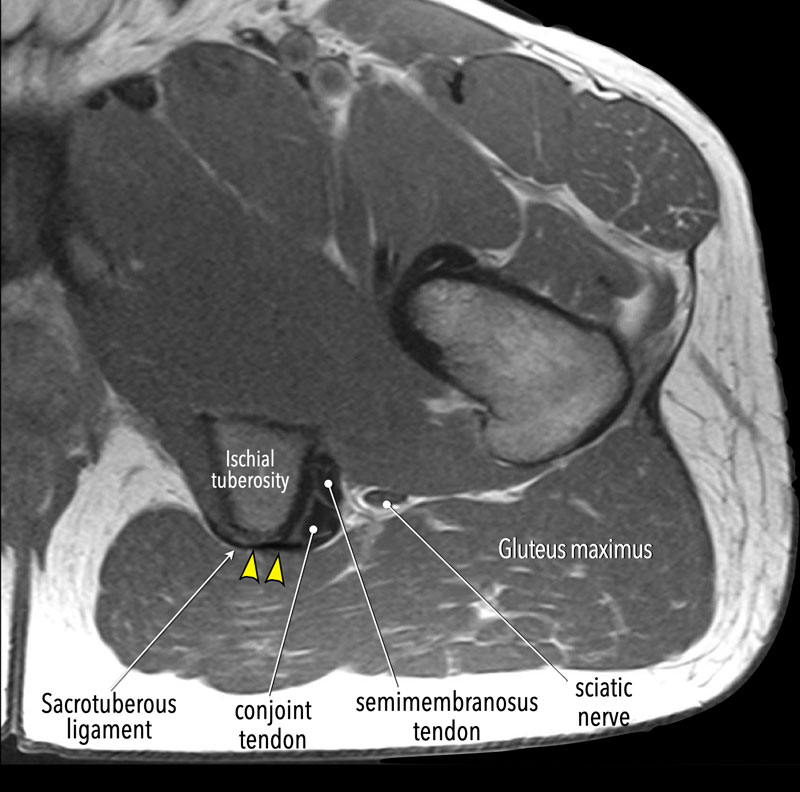

Il complesso del tendine del ginocchio è costituito da tre muscoli primari: il semimembranoso, il semitendinoso e il bicipite femorale (che ha teste sia lunghe che corte). Questi muscoli originano dall'aspetto posterolaterale della tuberosità ischiatica. In particolare, il bicipite femorale e il semitendinoso condividono un'origine tendinea congiunta, che si trova posteromedialmente all'origine del semimembranoso. L'impronta del tendine semimembranoso è posizionata leggermente anterolateralmente.

Il tendine congiunto misura circa 10 cm di lunghezza e corre tra il bicipite femorale, il capo lungo e il ventre del muscolo semitendinoso. Il capo lungo del bicipite femorale nasce dalla tuberosità ischiatica, appena distale al muscolo semitendinoso. Il bicipite femorale a testa corta ha un'origine più distale separata dalla linea aspera, una cresta sul femore posteriore. Queste origini distinte contribuiscono a diverse funzioni: la testa lunga è responsabile sia dell'estensione dell'anca che della flessione del ginocchio, mentre la testa corta flette principalmente il ginocchio.

Il tendine semimembranoso è il più lungo dei tendini prossimali del tendine del ginocchio, misurando circa 30 cm di lunghezza. Mentre scende, si appiattisce e si trova anteriormente al ventre del muscolo semitendinoso, posteriormente al muscolo magnus adduttore e medialmente al nervo sciatico. Il muscolo semimembranoso prossimale ha origine come un piccolo muscolo di forma triangolare dall'aspetto mediale di questo tendine appiattito. Quando il muscolo semimembranoso si estende caudalmente, si allarga e ha la più grande area della sezione trasversale dei muscoli posteriori della coscia, consentendogli di generare la massima forza.6